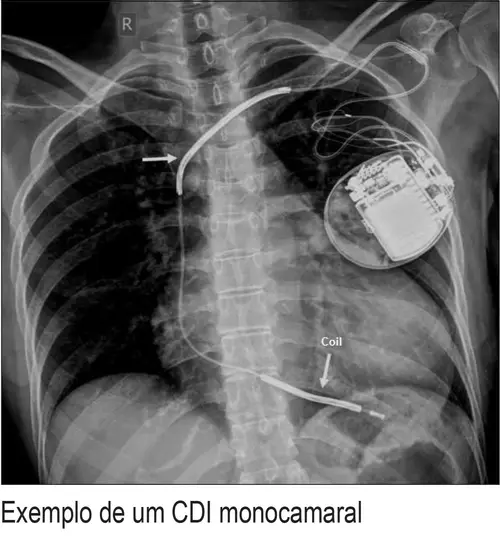

Desfibrilador Cardíaco Interno - Desfibrilador O Que E E Como Salvar Vidas Com O Equipamento / Los desfibriladores cardiacos han salvado muchísisimas vidas.. Rafael cardoso passa por cirurgia para implantar desfibrilador cardíaco. ¿para qué se utiliza el desfibrilador cardíaco? Un dai (desfibrilador cardiaco automático interno o desfibrilador cardioversor interno) es un dispositivo mecánico que controla la frecuencia y el ritmo cardíacos. El desfibrilador cardíaco es un dispositivo que produce una descarga eléctrica en el corazón y que puede ser de dos tipos, interno o externo. O implante do desfibrilador é semelhante ao implante do marca passo e a avaliação periódica é indispensável.

¿para qué se utiliza el desfibrilador cardíaco? Cirurgia de enxerto de artéria coronária. Es un seguro de vida contra arritmias muy graves. Após o implante, em geral realizamos uma avaliação em 1 semana, 3 meses e a cada. Desfibrilador interno o dai (desfibrilador automático implantable), es aquel que se implanta en la persona de la misma forma que un marcapasos. Un desfibrilador cardíaco es un aparato de electro medicina que analiza el ritmo del corazón y permite dar una descarga capaz de revertir la fibrilación ventricular. El desfibrilador automático implantable (dai) o cardiodesfibrilador recupera la frecuencia cardíaca con descargas eléctricas. El desfibrilador interno puede colocarse debajo de la piel de individuos con alto riesgo de sufrir paro cardíaco y, consecuentemente, muerte. Para que serve o desfibrilador cardíaco o desfibrilador cardíaco serve para tentar evitar a morte o desfibrilhador interno pode ser colocado debaixo da pele de indivíduos com alto risco de sofrerem. Adulto mayor esperó 24 días hospitalizado por cambio de batería de dispositivo cardíaco. Rafa passou por uma cirurgia para implantar um desfibrilador cardíaco. El desfibrilador externo automático (dea) es un dispositivo que analiza y busca ritmos cardíacos desfibrilables, notifica al preguntas frecuentes acerca del dea (desfibrilador externo automático). Desfibrilador interno, cirugía cardíaca mínimamente invasiva desfibrilador interno, ablación cardíaca, arritmia, extrasístole, fibrilación auricular, taquicardia supraventricular.